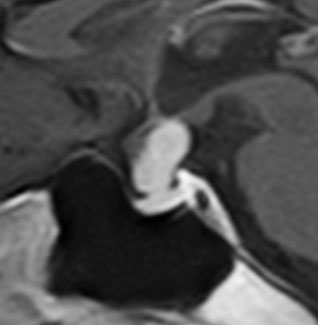

成人の下垂体柄に発生した小さな頭蓋咽頭腫です。のう胞性ですが石灰化もあり術前診断は可能でした。この頭蓋咽頭腫は,下垂体柄の内部から発生したものですから,下垂体柄が全周にわたってfunningしています。ちょうど前庭神経鞘腫における顔面神経のようなものです。また,冠状断で見ると下垂体柄が左に寄っているのが推測できますから,右側からアプローチします。腫瘍を観察しても,最初のうちは下垂体柄がどこにあるのかは解りません。